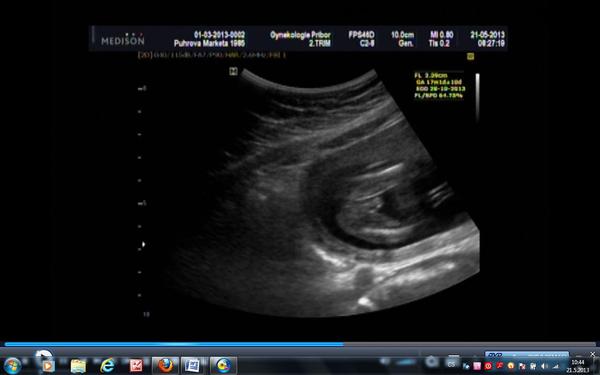

Ahoj maminky a budoucí maminky 😉 Prosím, poradila byste mi některá, co vidíte na fotce z ultrazvuku ve 20. týdnu za pohlaví? Určitě jste foteček viděly už mraky, proto vás žádám o radu...Nechci nikoho ovlivnit, proto svůj tip řeknu později 🙂 Děkuju moc!!!

Tak jen pro info - na původní fotce k tématu - je to kluk! 🙂 Zakladatelka